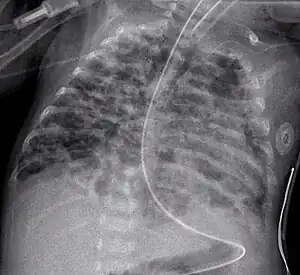

Displasia broncopulmonar é uma doença pulmonar crónica em recém-nascidos e crianças. É mais comum em crianças com baixo peso à nascença e nas que se submetem a tratamentos prolongados com ventilação mecânica para a síndrome da angústia respiratória do recém-nascido. A doença causa morbilidade e mortalidade significativas. Foi descrita pela primeira vez em 1967.[1]